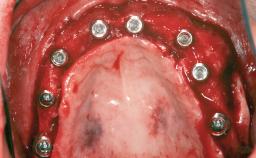

A 47-year-old woman who had suffered from aggressive periodontitis requiring a number of periodontal interventions over more than 10 years was referred by her general dental practitioner and periodontologist for bone augmentation and implant therapy. Her failing dentition had already been scheduled for extraction. The patient expressed a desire for implant-supported fixed restorations and esthetic improvement of her lower face. She had agreed to consult with a maxillofacial surgeon after the referring dentist had suggested bone augmentation. An initial examination by the maxillofacial surgeon revealed mobility of all residual teeth in a patient who was very unhappy with the function of her removable partial dentures. Due to periodontally migrated flaring teeth and loss of occlusal support, the vertical dimension of occlusion was dramatically reduced. The patient was displeased with her lower face because of deepened nasolabial, commissural, and supramental folds.

# of Implants 14

Type of Implants Two-Piece